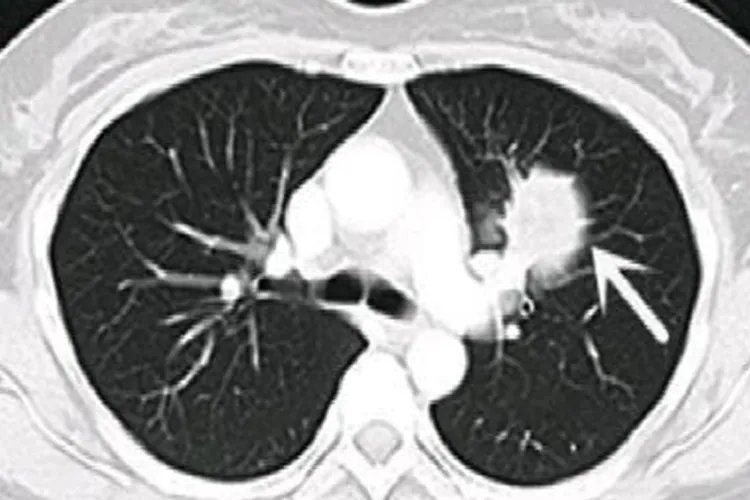

肺部霉菌感染肺部霉菌感染可无明显呼吸道症状,但可因合并细菌感染出现明显的咳嗽、咳痰、发热等表现。影像学检查可发现肺内散在分布大小不一的小结节,并晕轮的块状影、多个透明空洞。